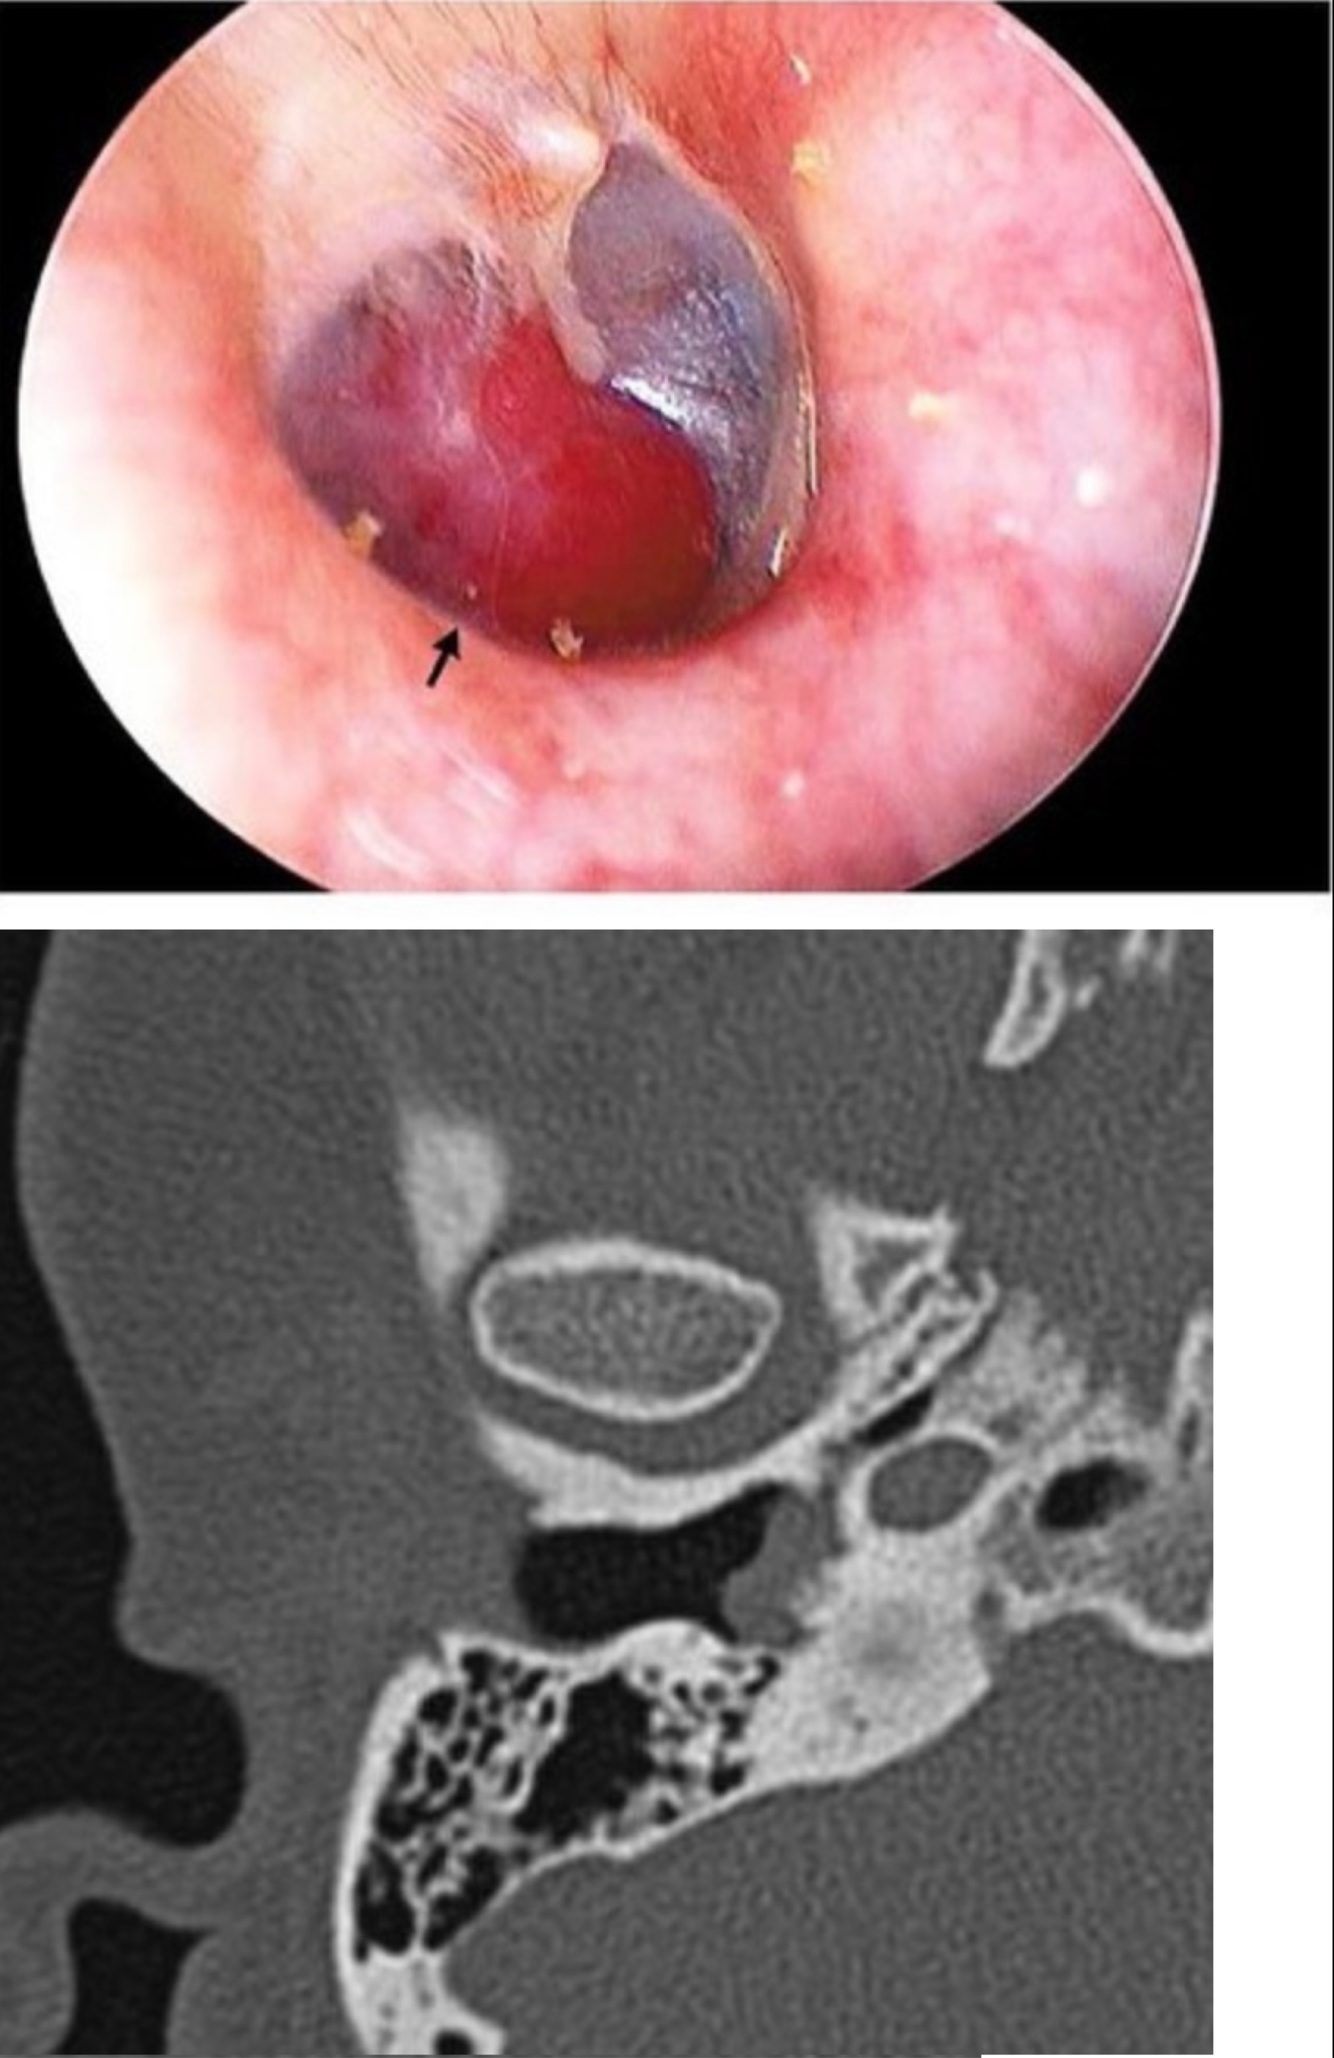

57M w/presents for evaluation of R-pulsation tinnitus that has been present for several mos. An audiogram shows normal hearing on the L and a moderate CHL on the R. Otoscopy on the R is shown in the image. CT images are also shown below. What is the diagnosis?

A

Tympanic paraganglioma tumors (glomus tympanicum) - arises from glomus body of the promontory along Jacobson’s n.

Q

57M w/presents for evaluation of R-pulsation tinnitus that has been present Xooms. An audiogram shows normal hearing on the L and a moderate CHL on the R. Otoscopy on the R is shown in the image. CT images are also shown below. What is the most reasonable next step in management of his ear mass?

The dx is made clinically, and next step is further imaging w/MRI (provides superior soft tissue and vascular resolution).